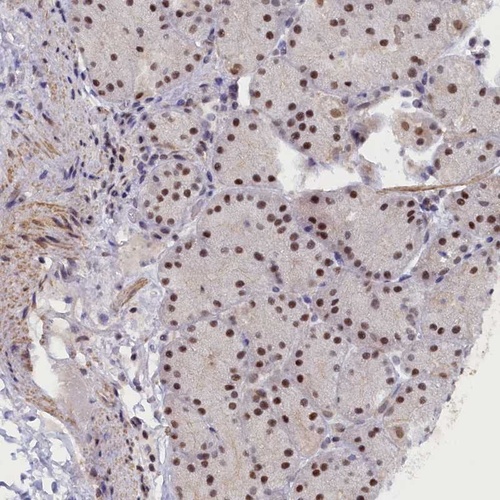

Immunohistochemical staining of human stomach, lower shows strong nuclear positivity in glandular cells.